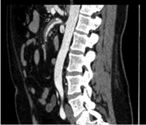

Bertolotti’s syndrome: an underdiagnosed cause for lower back pain

Francisco Alonzo and others

Journal of Surgical Case Reports, Volume 2018, Issue 10, October 2018, rjy276, https://doi.org/10.1093/jscr/rjy276